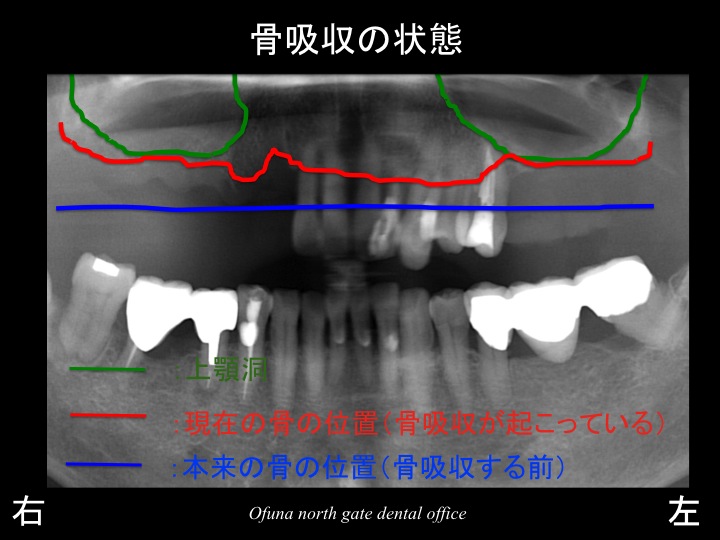

ここで いつものように 骨吸収の状態を分かりやすくするために

骨吸収の状態を線で書いたのが以下のレントゲンになります。

青線が骨吸収を起こす前の骨の位置です。

赤線は、現在の骨の位置です。

緑線は上顎洞です。

上顎洞(緑線の上方)は空洞です。

骨ではなく、穴が開いているのです。

上顎の右側の奥歯では、骨吸収と上顎洞の存在により骨の高さがほとんどないことが分かるかと思います。

上顎右側の奥歯において 現時点で存在する骨の高さは、約1ミリです。

骨の高さが1ミリしか存在しなければ、インプラント治療は無理です。